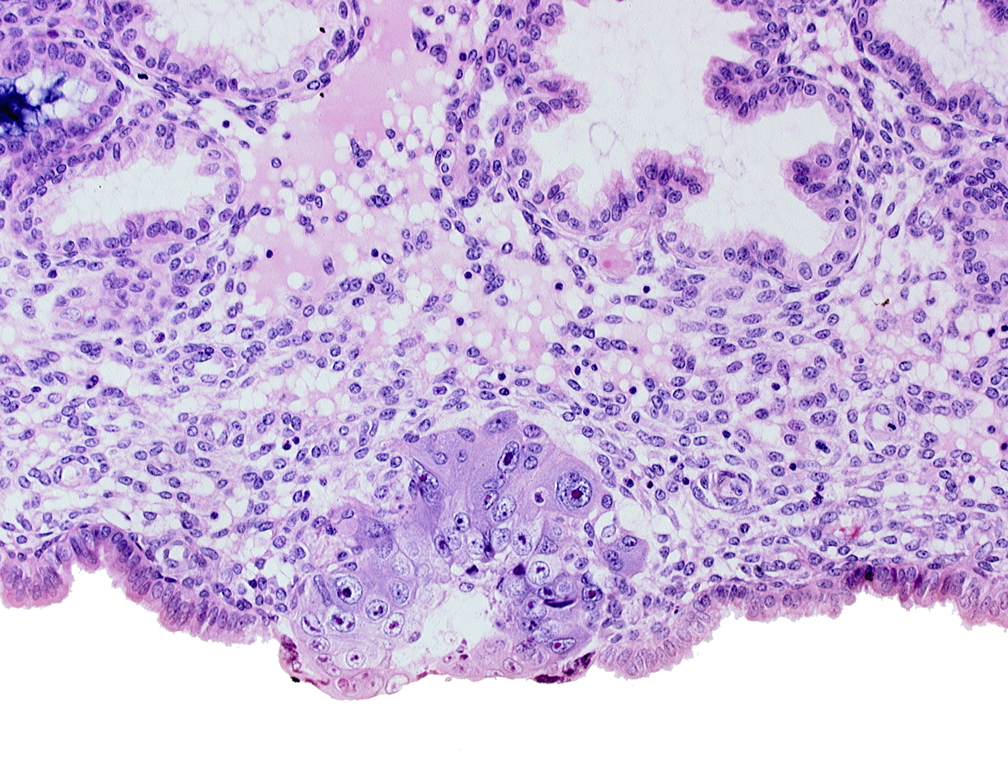

Carnegie Embryo #8155 | Location: 04-03-04

Keywords: blastocystic cavity (blastocoele), cytotrophoblast, edge of membranous trophoblast at abembryonic pole, solid syncytiotrophoblast